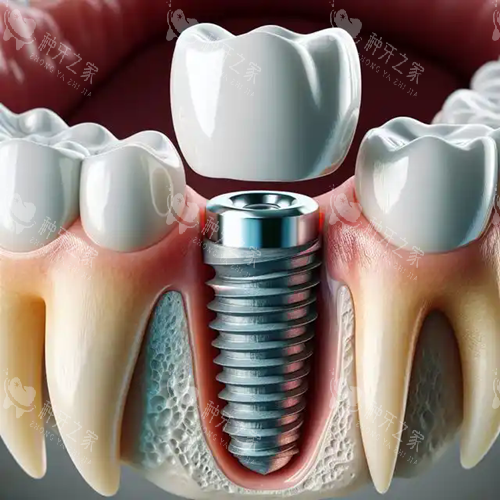

种植牙作为一种理想的牙齿修复方式,能够比较大程度地改善牙齿的功能和美观,越来越受到老年人的青睐。

中诺口腔引进了一系列国内外靠前的口腔种植设备和技术,如口腔 CT 扫描仪、种植导航系统等。

这些设备和技术能够为医生提供较准的口腔数据和图像,帮助医生更比较准地进行种植手术。

例如,种植导航系统可以在术前模拟种植过程,确定种植体的位置、角度和深度,大大提高了手术的成功概率和可靠性。